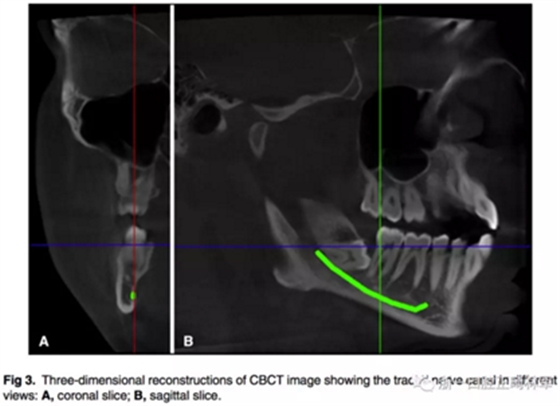

下牙槽神經(jīng)管通過(guò)軟件電子示蹤。(圖3)